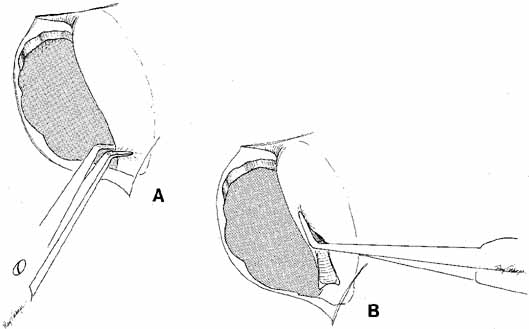

a distal obstruction is present at the valve of Hasner.  Fig. 20 Infracture of the inferior turbinate. A periosteal elevator is slipped

into the inferior meatus and advanced along the length of the inferior

turbinate. The patient's head is stabilized and the turbinate is

pushed medially by distributing force along the entire length of the

turbinate rather than just at one point. This step creates a larger space

for the exit of tears from the nasolacrimal duct and minimizes trauma. The

instillation of oxymetazoline (Afrin, Schering, Liberty

Corners, NJ) into the inferior meatus before this maneuver will reduce

intraoperative and postoperative bleeding. Fig. 20 Infracture of the inferior turbinate. A periosteal elevator is slipped

into the inferior meatus and advanced along the length of the inferior

turbinate. The patient's head is stabilized and the turbinate is

pushed medially by distributing force along the entire length of the

turbinate rather than just at one point. This step creates a larger space

for the exit of tears from the nasolacrimal duct and minimizes trauma. The

instillation of oxymetazoline (Afrin, Schering, Liberty

Corners, NJ) into the inferior meatus before this maneuver will reduce

intraoperative and postoperative bleeding.